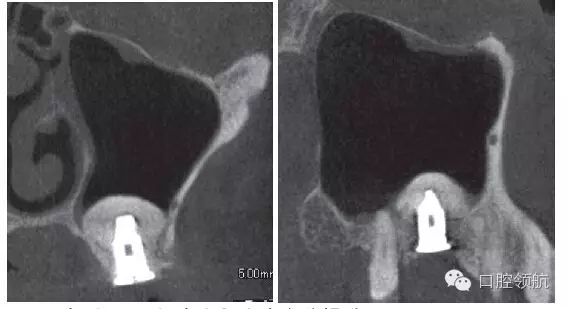

因為垂直骨量少,在植入種植體后,為防止種植體進入上頜竇內,選擇了安裝直徑大的覆蓋螺絲(圖5、圖6)。 術后CBCT證實上頜竇底提升了足夠的骨量(圖7)。

圖7 術后CBCT證實上頜竇底充分提升。

術后12周在獲得骨結合后,開始制作上部結構,術后16周戴入(圖8)。術后24周,CBCT影像顯示,種植體周圍有足夠的骨量(圖9)。

圖9 術后24周,CBCT影像顯示通過拔牙后早期植入,能夠進行安全確實的上頜竇底提升術。